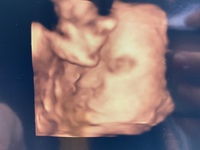

36週臨月での風邪、微熱 4歳の息子が痰の絡む咳をし始めて2日後の金曜日夜3の発熱。 翌日には微熱に移行し、月曜日には平熱に。 咳はまだ残ってる状態です。 その風邪を貰ってしまったらしく、私の方も月曜日から喉の痛み、火曜日は安静に寝ており 臨月になると気になるのが、いつ赤ちゃんが生まれてくるかということ。 予定日ぴったりに生まれる、という訳ではないので、その時がいつ来るのか、とっても気になりますよね。 出産の兆候と言うのも同時に気になるでしょう。 臨月になると出てくる症状に妊娠初期の微熱はいつまで続くのか 妊娠初期の微熱は、13週を過ぎた頃から 下がり始めます。 それまでは高体温が続き、 平熱より約03℃上がりますが 妊娠中期になると平熱に戻ります。 私は平熱が低いのですが、6週頃に 基礎体温を測ると平熱より0

臨月 風邪 微熱-妊娠していれば最終月経から微熱がずっと続くことになります。 妊娠中の体温は、妊娠中期の24週ごろまでには、 大体の人が平常の熱に戻ることが多いです。 また、妊娠後期の臨月が近くなってくると、 赤ちゃんの成長と共に微熱を感じるという人もい 妊娠初期(妊娠12、13週頃まで) 妊娠すると、高温期と呼ばれる平均367度以上をキープする状態が続きます。 妊娠すると赤ちゃんがお腹の中で育ち始めます。 母体は妊娠をキープするために高温状態を保ちます。 これは、ホルモンの影響によるものです

妊婦の発熱の下げ方|胎児に影響は? 病院は何度から? お風呂も医師監修 「熱が下がらない・・・病院に行くべき? 」 妊婦さんの熱の原因と対処法について、お医者さんが解説。 お風呂や食事についても聞いたので、参考にしてくださいね。臨月 微熱 だるい — 臨月に入ると、妊娠初期のようなだるさ、熱っぽさを感じる妊婦さんがいますが、主な原因は次に挙げるような臨月の母体の変化にあります。 疲れやすくなっている 臨月に入っても、胎児はまだまだ大きく成長し、妊婦さんのお腹は大きくなっ?